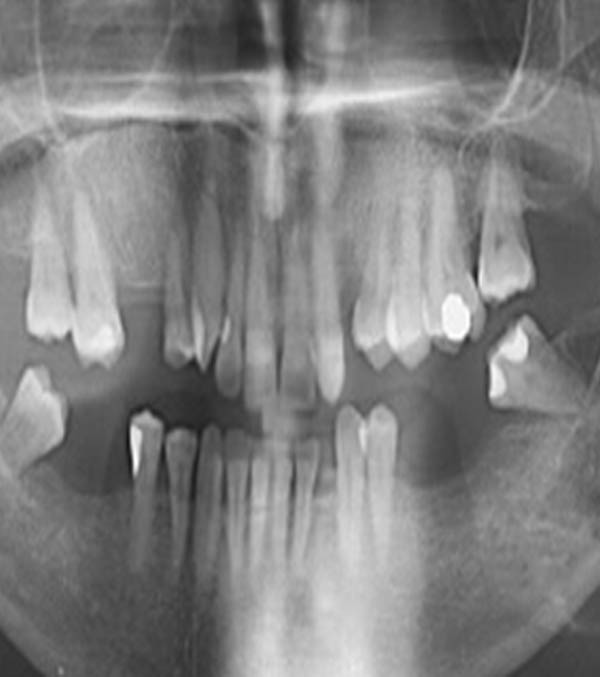

Facial pain may be caused by many conditions such as toothache, infections around the teeth or jaws, sinus disease from the upper jaws, neuralgia and rarely cancer from the oral, nasal or throat cavities.

Diagnosis is made by taking a full and careful history of the pain and, if required, x-rays and/or scans. This may well involve liaising with other specialists such as neurologists, clinical psychologists, psychiatrists, pain clinic specialists and rarely neurosurgeons.

Enlongated Bone Causing Facial Pain